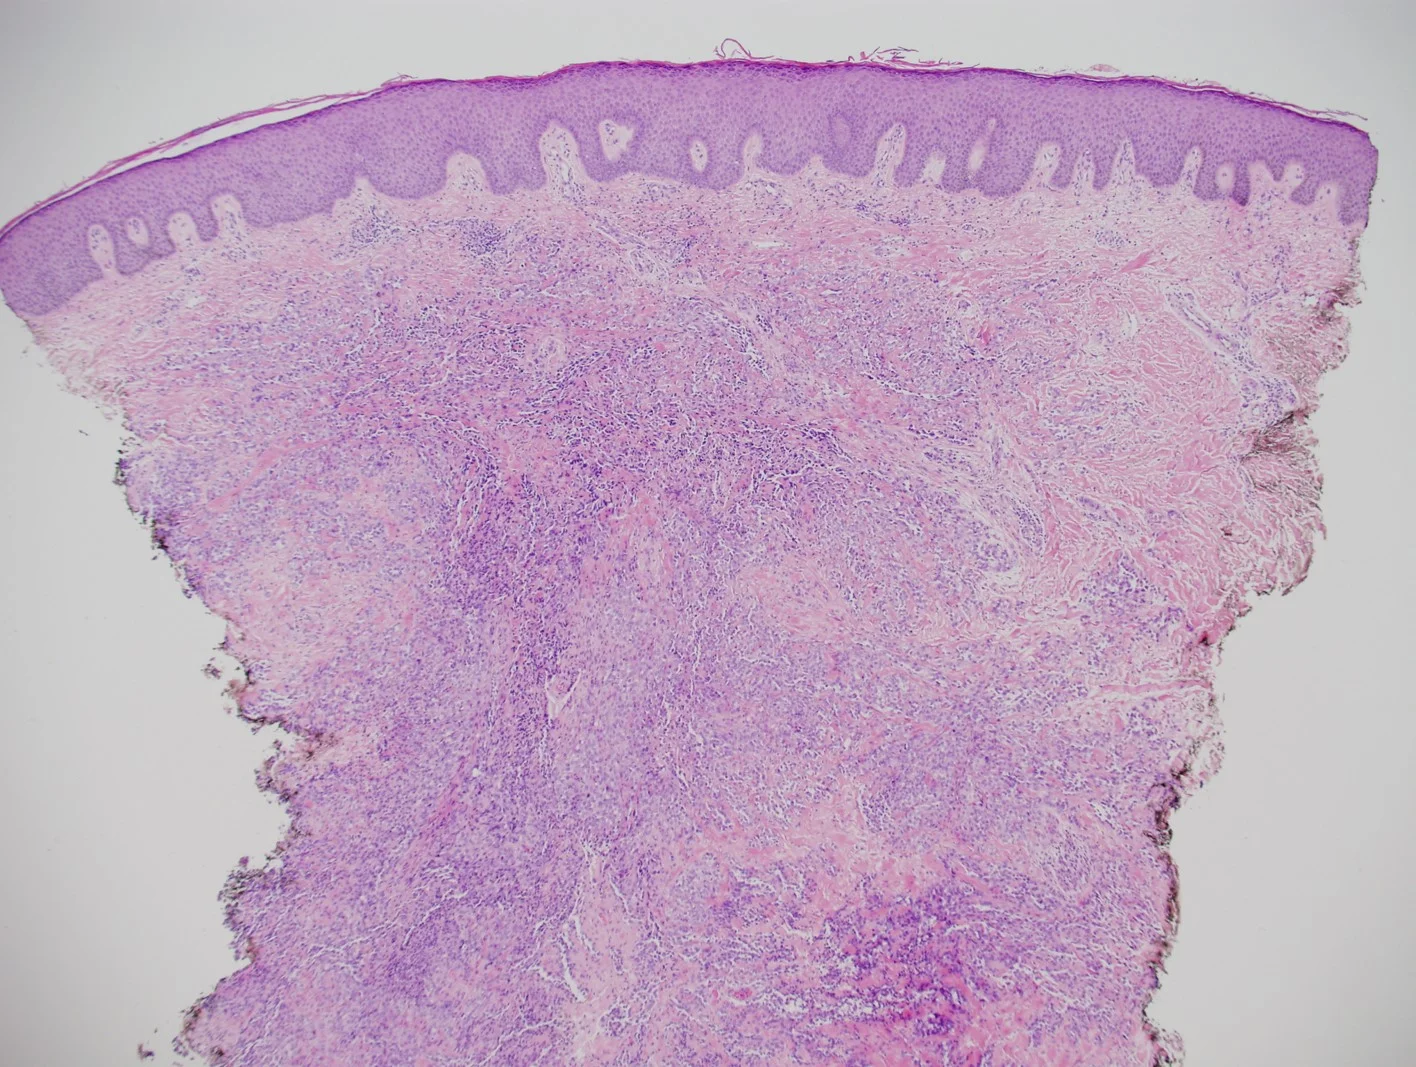

Histopathology: The sections showed a dense superficial and deep perivascular, perifollicular, and interstitial lymphoid infiltrate extending into the subcutaneous tissue. The lymphocytes were pleomorphic, intermediate to large, with irregular chromatin distribution and scattered mitoses. The overlying epidermis demonstrated subtle interface vacuolization with scattered single and collections of lymphocytes, suggestive of epidermotropism. There was no significant necrosis or vasculitis, but extravasation of erythrocytes with riming of fat by atypical lymphocytes was seen.

The histologic differential diagnoses included plaque and tumor stage mycosis fungoides, pseudolymphomatous lupus panniculitis, cytotoxic subcutaneous panniculitis-like-T-cell lymphoma and primary cutaneous gamma/delta T cell lymphoma.

Immunohisochemical evaluation revealed tumor cells to be positive for CD2, CD3, CD56, TIA-1, and granzyme B, and negative for CD5, CD7, CD4, CD8, CD20, and CD123. Additionally, CD 30, Beta FI Gamma M1 were also negative. EBV-encoded RNA (EBER)-1 in situ hybridization was positive for EBV mRNA. RT-PCR T-Cell gene arrangement study was positive.

The histology and staining profile were consistent with EBV positive Extranodal NK/T-Cell Lymphoma.